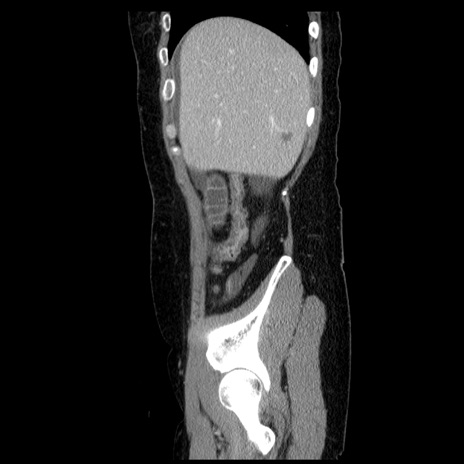

症例6(矢状断像)

【症例】50歳代女性

【主訴】下腹部痛

【既往歴】卵巣癌術後(8年前に当院で卵巣摘出)

【身体所見】 意識清明、腹部:平坦、腸蠕動音→、やや硬、下腹部自発痛・圧痛あり、反跳痛あり、筋性防御なし。

【データ】WBC 16000、CRP 0.01